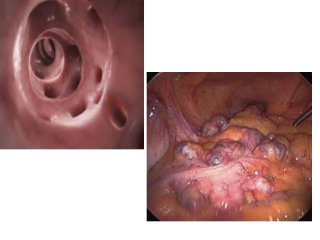

Endoscopy

• Diverticulosis is frequently discovered during

colonoscopy as an incidental finding

• Flexible sigmoidoscopy is necessary only if

carcinoma or colitis is a concern

• Colonoscopy is relatively contraindicated in

patients in whom acute diverticulitis is

suspected, due to an increased risk of colonic

perforation.

• patients who have not previously had a

colonoscopy should have one to exclude an

underlying malignancy or other disorder, with

a waiting period of 6–8 weeks following

resolution of the episode of diverticulitis. If an

endoscopy is to be performed in order to

differentiate between acute diverticulitis and

cancer or colitis prior to surgery, it should only

be attempted by an experienced endoscopist,

with minimal insufflation.